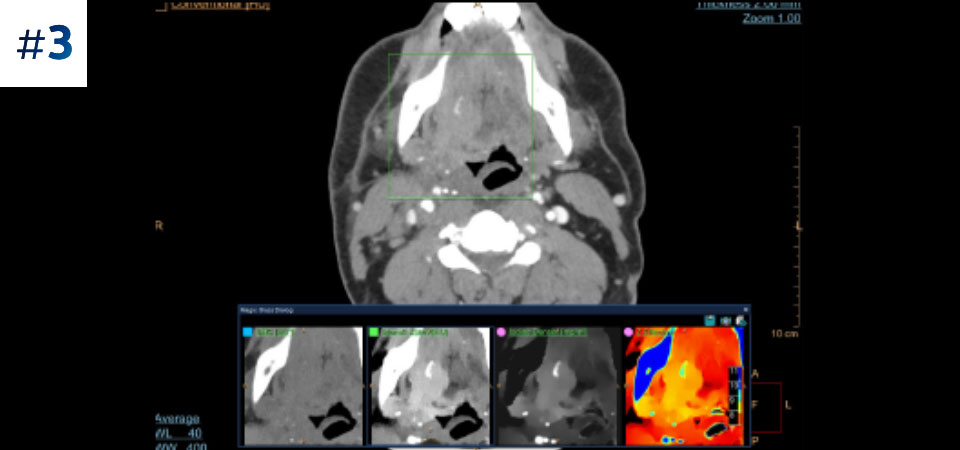

Umflătură la nivelul gâtului